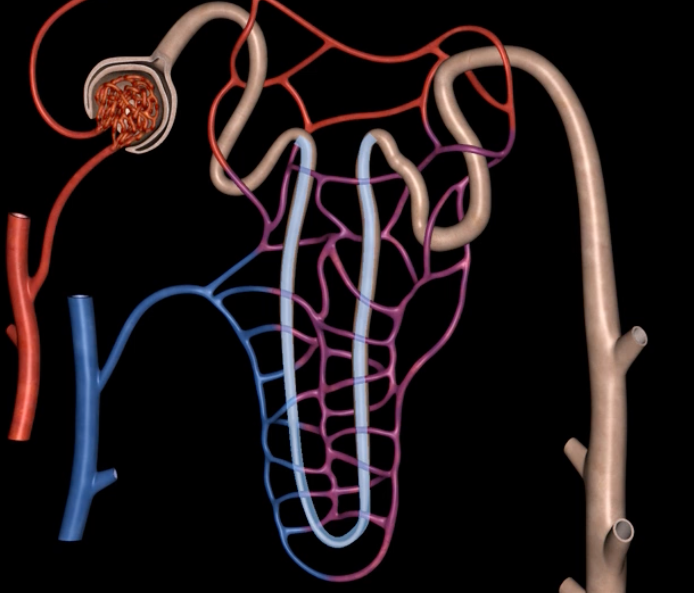

afferent arteriole

yellow

glomerulus

green

efferent arteriole

purple

orange: peritubular capillaries

green: vasa recta

efferent arteriole give rise to orange and green

interlobular vein

segmental artery

interlobar vein

arcuate artery